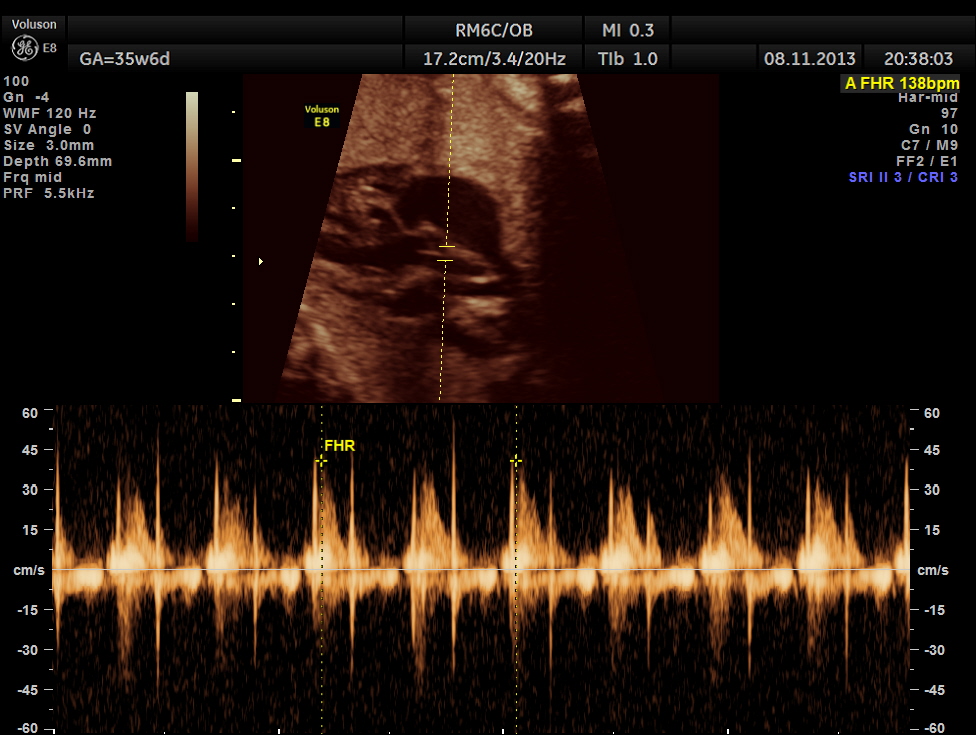

The scan was repeated at 36 weeks of gestation.

the umbilical artery doppler appears normal.